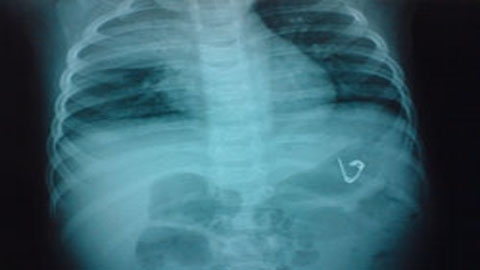

Tại bệnh viện, các bác sĩ kết luận bệnh nhi có chiếc một chiếc kim băng mở bung nằm trong bụng. Bé Đ. đã rất may mắn vì ruột và thực quản không bị mũi nhọn của kim băng chọc trúng gây tổn thương.

Sau một ngày theo dõi, chiếc kim băng trên đã tự thoát ra khỏi cơ thể bệnh nhi theo đường tự nhiên.